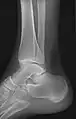

- Ankle - AP/Mortice and Lateral

Ankle - frontal

15 degrees internal rotation

Lateral (this one a bit suboptimal by not seeing straight through the ankle joint)

Lateral oblique (to visualize the posterior border of the tibia)